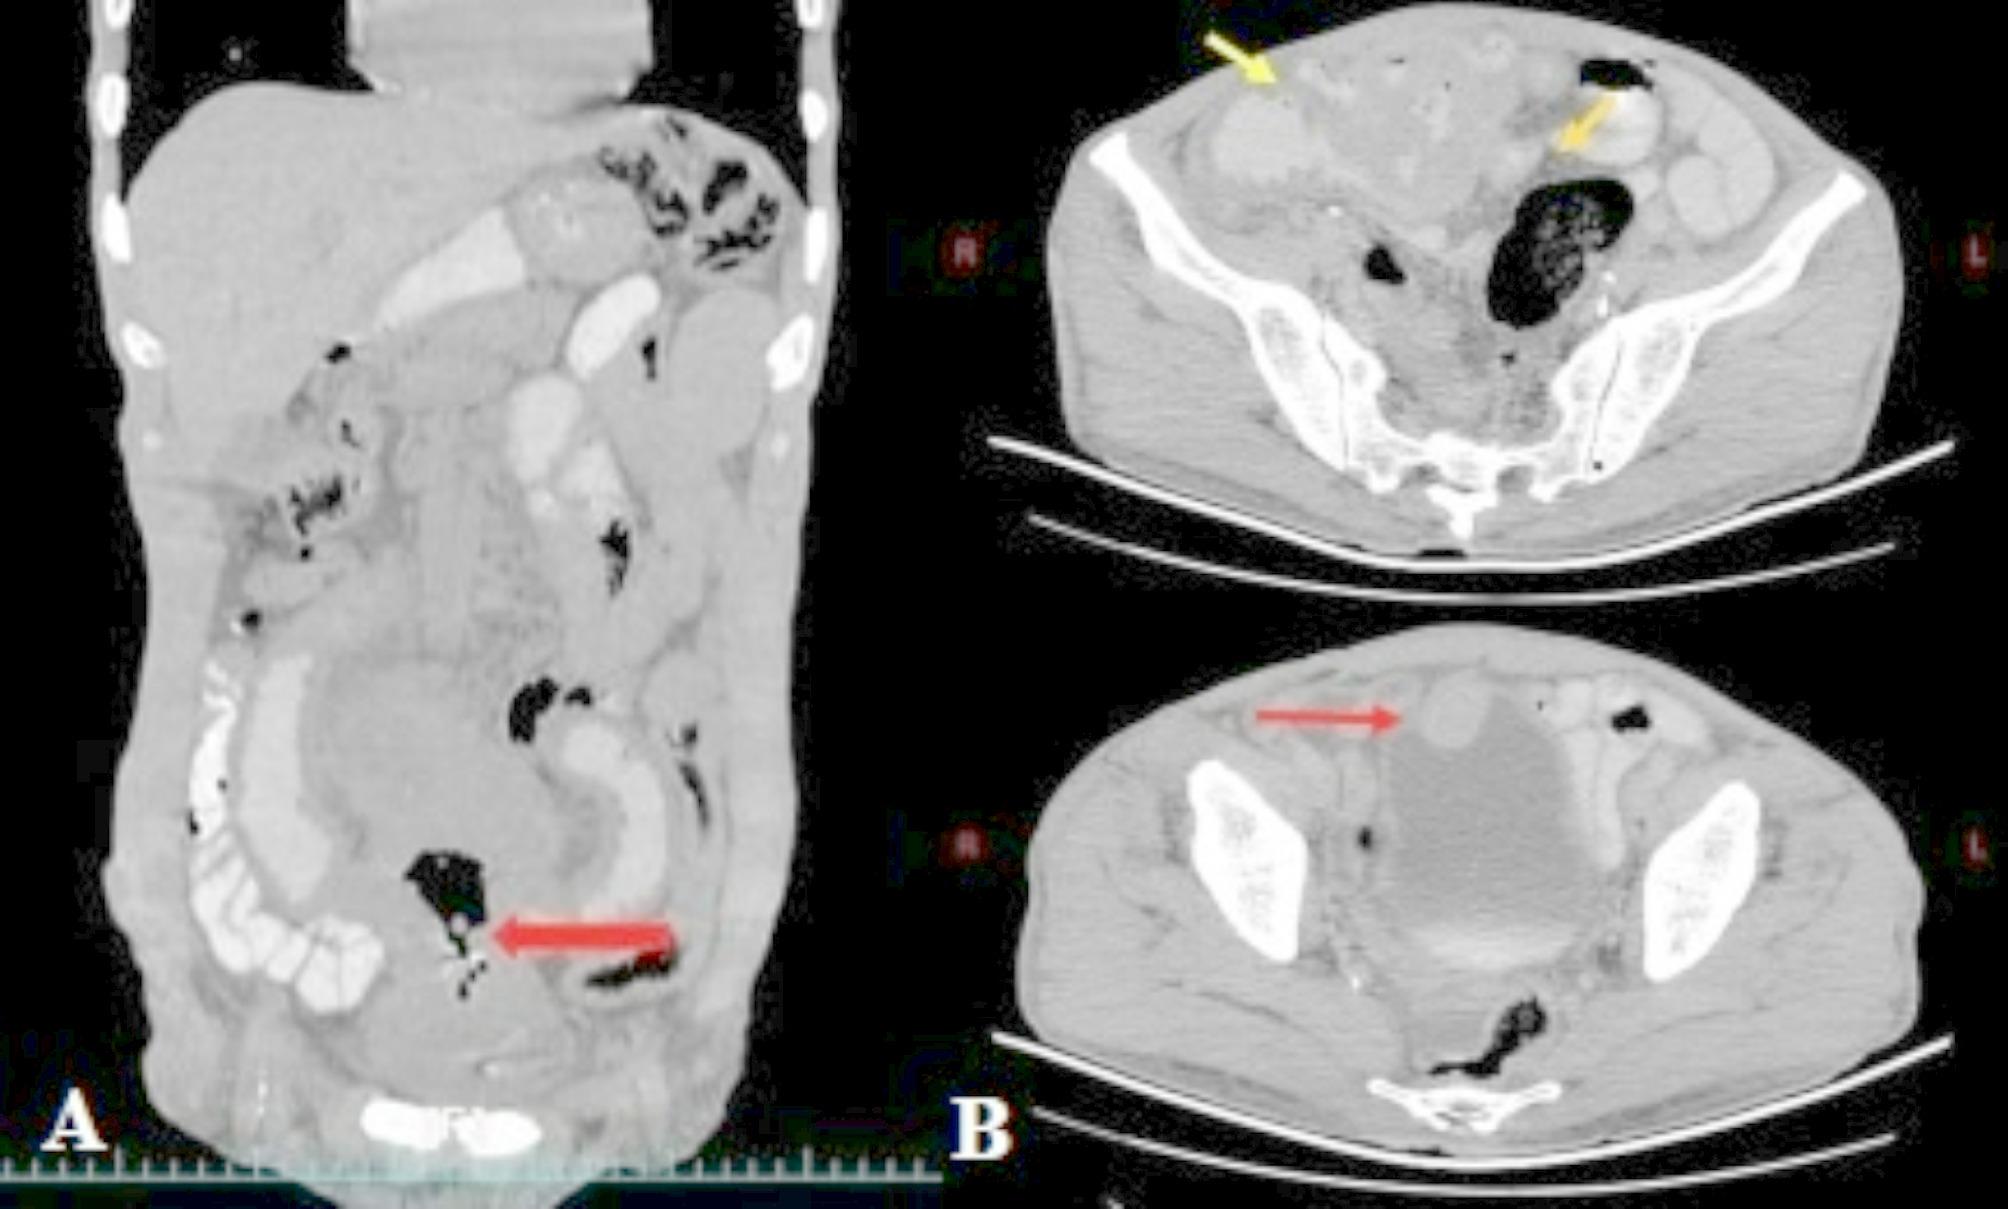

里希特转化(RT)是慢性淋巴细胞白血病(CLL)的罕见并发症,可导致侵袭性大b细胞淋巴瘤或霍奇金淋巴瘤。在此,我们报告一例罕见的由慢性淋巴细胞白血病(CLL)的移植引起的肠膀胱瘘(EVF)。一名患有慢性淋巴细胞白血病的59岁白人男性因下胃剧烈腹痛来到血液科就诊。超声检查显示回肠一段伴邻近淋巴结病变的壁厚增加,提示淋巴瘤累及。化疗后一天,患者主诉血尿。他做了膀胱镜检查,没有发现异常。膀胱镜检查后,患者血尿停止,但主诉尿液中含有前一天的食物。患者的CT膀胱造影结果正常。然而,腹部骨盆CT扫描显示空肠远端小肠袢厚度增加,未见梗阻,提示淋巴瘤累及。根据患者的粪尿情况,他顺利地接受了手术,并证实了EVF。切除受累小肠及部分膀胱。病理结果提示CLL转为弥漫性大b细胞淋巴瘤(DLBCL)。EVF不仅可能是CLL的罕见并发症,而且由于疾病的特点或治疗的结果,它也可能在接受RT的患者中表现出来。对于临床医生管理CLL患者来说,了解RT及其并发症是至关重要的。

Richter transformation (RT) is an uncommon complication of chronic lymphocytic leukemia (CLL) that can lead to aggressive large B-cell lymphoma or Hodgkin lymphoma. Here, we present a rare case of enterovesical fistula (EVF) resulting from RT of CLL. A 59-year-old Caucasian male with CLL visited the hematology department with severe abdominal pain in the hypogastrium. Ultrasonography showed an increase in wall thickness in a segment of the ileum with adjacent lymphadenopathy, indicating lymphomatous involvement. A day after receiving chemotherapy, the patient complained of hematuria. He underwent a cystoscopy, which revealed no abnormal findings. After the cystoscopy, the patient's hematuria stopped, but he complained about the excretion of food from the previous day in his urine. The patient's CT cystography results were normal. However, the abdominopelvic CT scan revealed an increase in the thickness of the small intestine loops in the distal part of the jejunum without any evidence of obstruction, suggesting lymphomatous involvement. Based on the patient's fecaluria, he uneventfully underwent surgery, and EVF was confirmed. Resection of the involved small intestine and partial cystectomy were done. The pathology results suggested RT of CLL to diffuse large B-cell lymphoma (DLBCL). Not only EVF might be an uncommon complication of CLL, but it could also manifest in patients undergoing RT due to the disease's characteristics or as a result of treatment. It is essential for clinicians managing CLL patients to be aware of the RT and its complications.